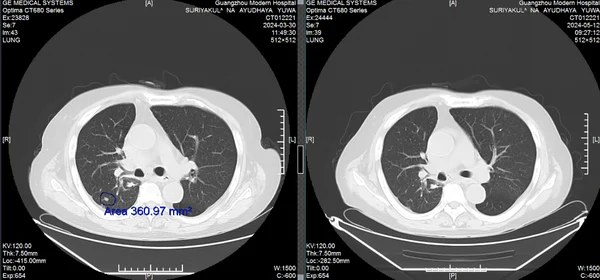

70-летний Сурьякул На Аюдхая Ювануд нашел спасение в малоинвазивных технологиях после рецидива рака

В 2021 году у генерала Ювануда из Таиланда диагностировали рак легких. Несмотря на операцию и курсы химиотерапии, болезнь вернулась с метастазами. Возраст и гипертония сделали дальнейшее традиционное лечение невозможным. К 2023 году состояние ухудшилось: одышка, слабость, необходимость в инвалидном кресле. Семья не сдалась. По рекомендации друга, победившего рак гортани в той же клинике 10 лет назад, генерал обратился в Modern Cancer Hospital Guangzhou.

Прорыв: комплекс малоинвазивных методов

Мультидисциплинарная команда клиники разработала персонализированный план: 1. Интервенционная терапия - доставка химиопрепаратов непосредственно в опухоль через артерии. 2. Имплантация радиоактивных частиц - точечное уничтожение метастазов. 3. Иммунотерапия - активация собственных защитных сил организма. Результат через 2 курса лечения: • Опухоль уменьшилась на 60%. • Исчезли одышка и необходимость в инвалидном кресле. • Риск синдрома верхней полой вены устранен. «Интервенционная терапия бьет точно в цель, не затрагивая здоровые ткани. Это главное преимущество», - отмечает супруга генерала.